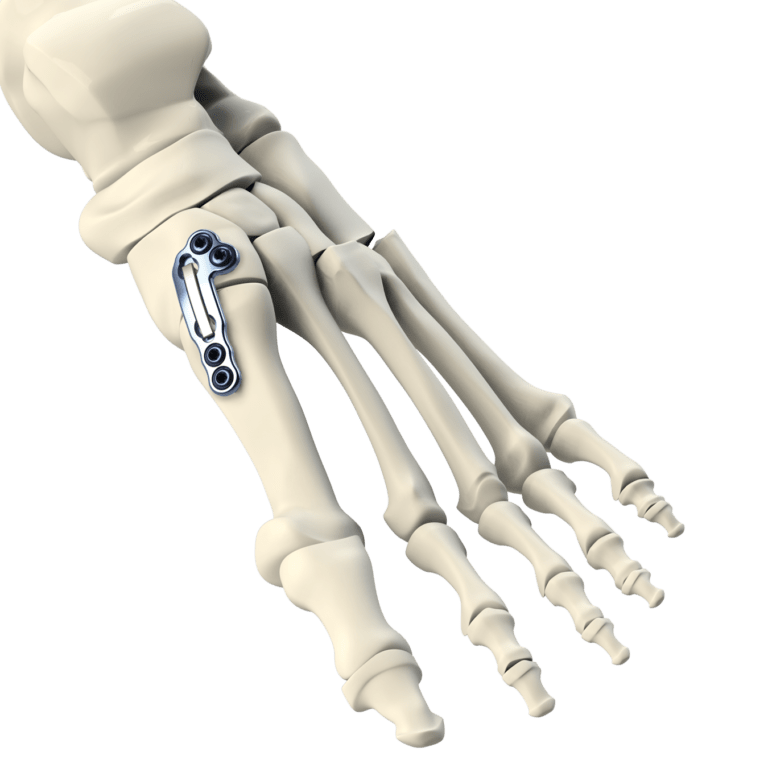

Медицинские решения: Операция по коррекции Hallux valgus